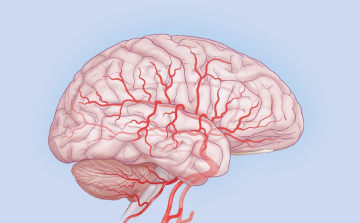

Agyrázkódás: a tünetek elmúltával is érezteti hatását

Kutatók sikeresen hallgatták le az agyhullámokat

A Stanford Egyetem kutatói rohamok során jelentkező agyi aktivitást konvertáltak zenévé.